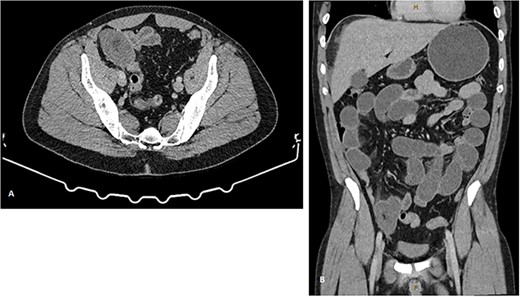

A gentleman in his forties presented to the emergency department with obstipation, nausea, and vomiting. He was previously fit and well, with no significant past medical or surgical history. He admitted consumption of a large quantity of mangoes in the lead up to his presentation; the number of which he was unable to quantify. Physical examination revealed a well looking patient, with normal dentition, mild dehydration, and abdominal distention without peritonism. Computer tomography (CT) demonstrated a small bowel obstruction (SBO) with a transition point (TP) in the right lower quadrant, with no evidence of perforation or closed loop formation (Fig. 1).

CT images demonstrating small bowel obstruction with TP in the right iliac fossa. (A) representative axial imaging slice, and (B) representative coronal slice.